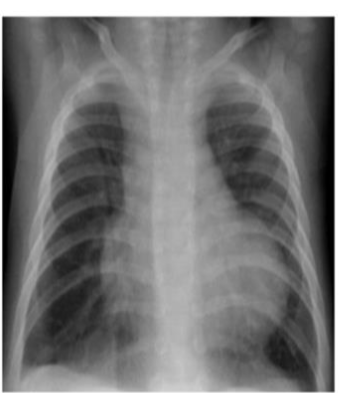

X-Ray with Consolidation:

- What is the diagnosis? Pneumonia

- What is the causative organism? Streptococcus Pneumonia